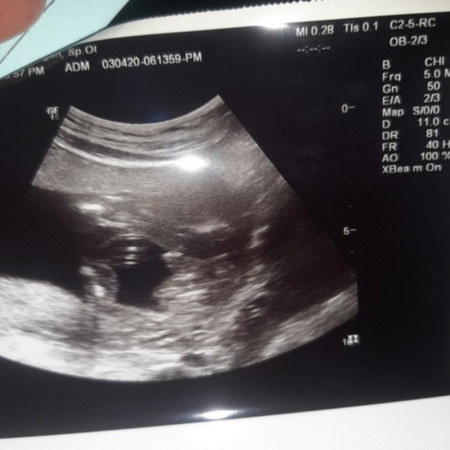

kehamilan

Bunda, aku masih kurang mengerti soal USG ini? Ini tandanya apa?